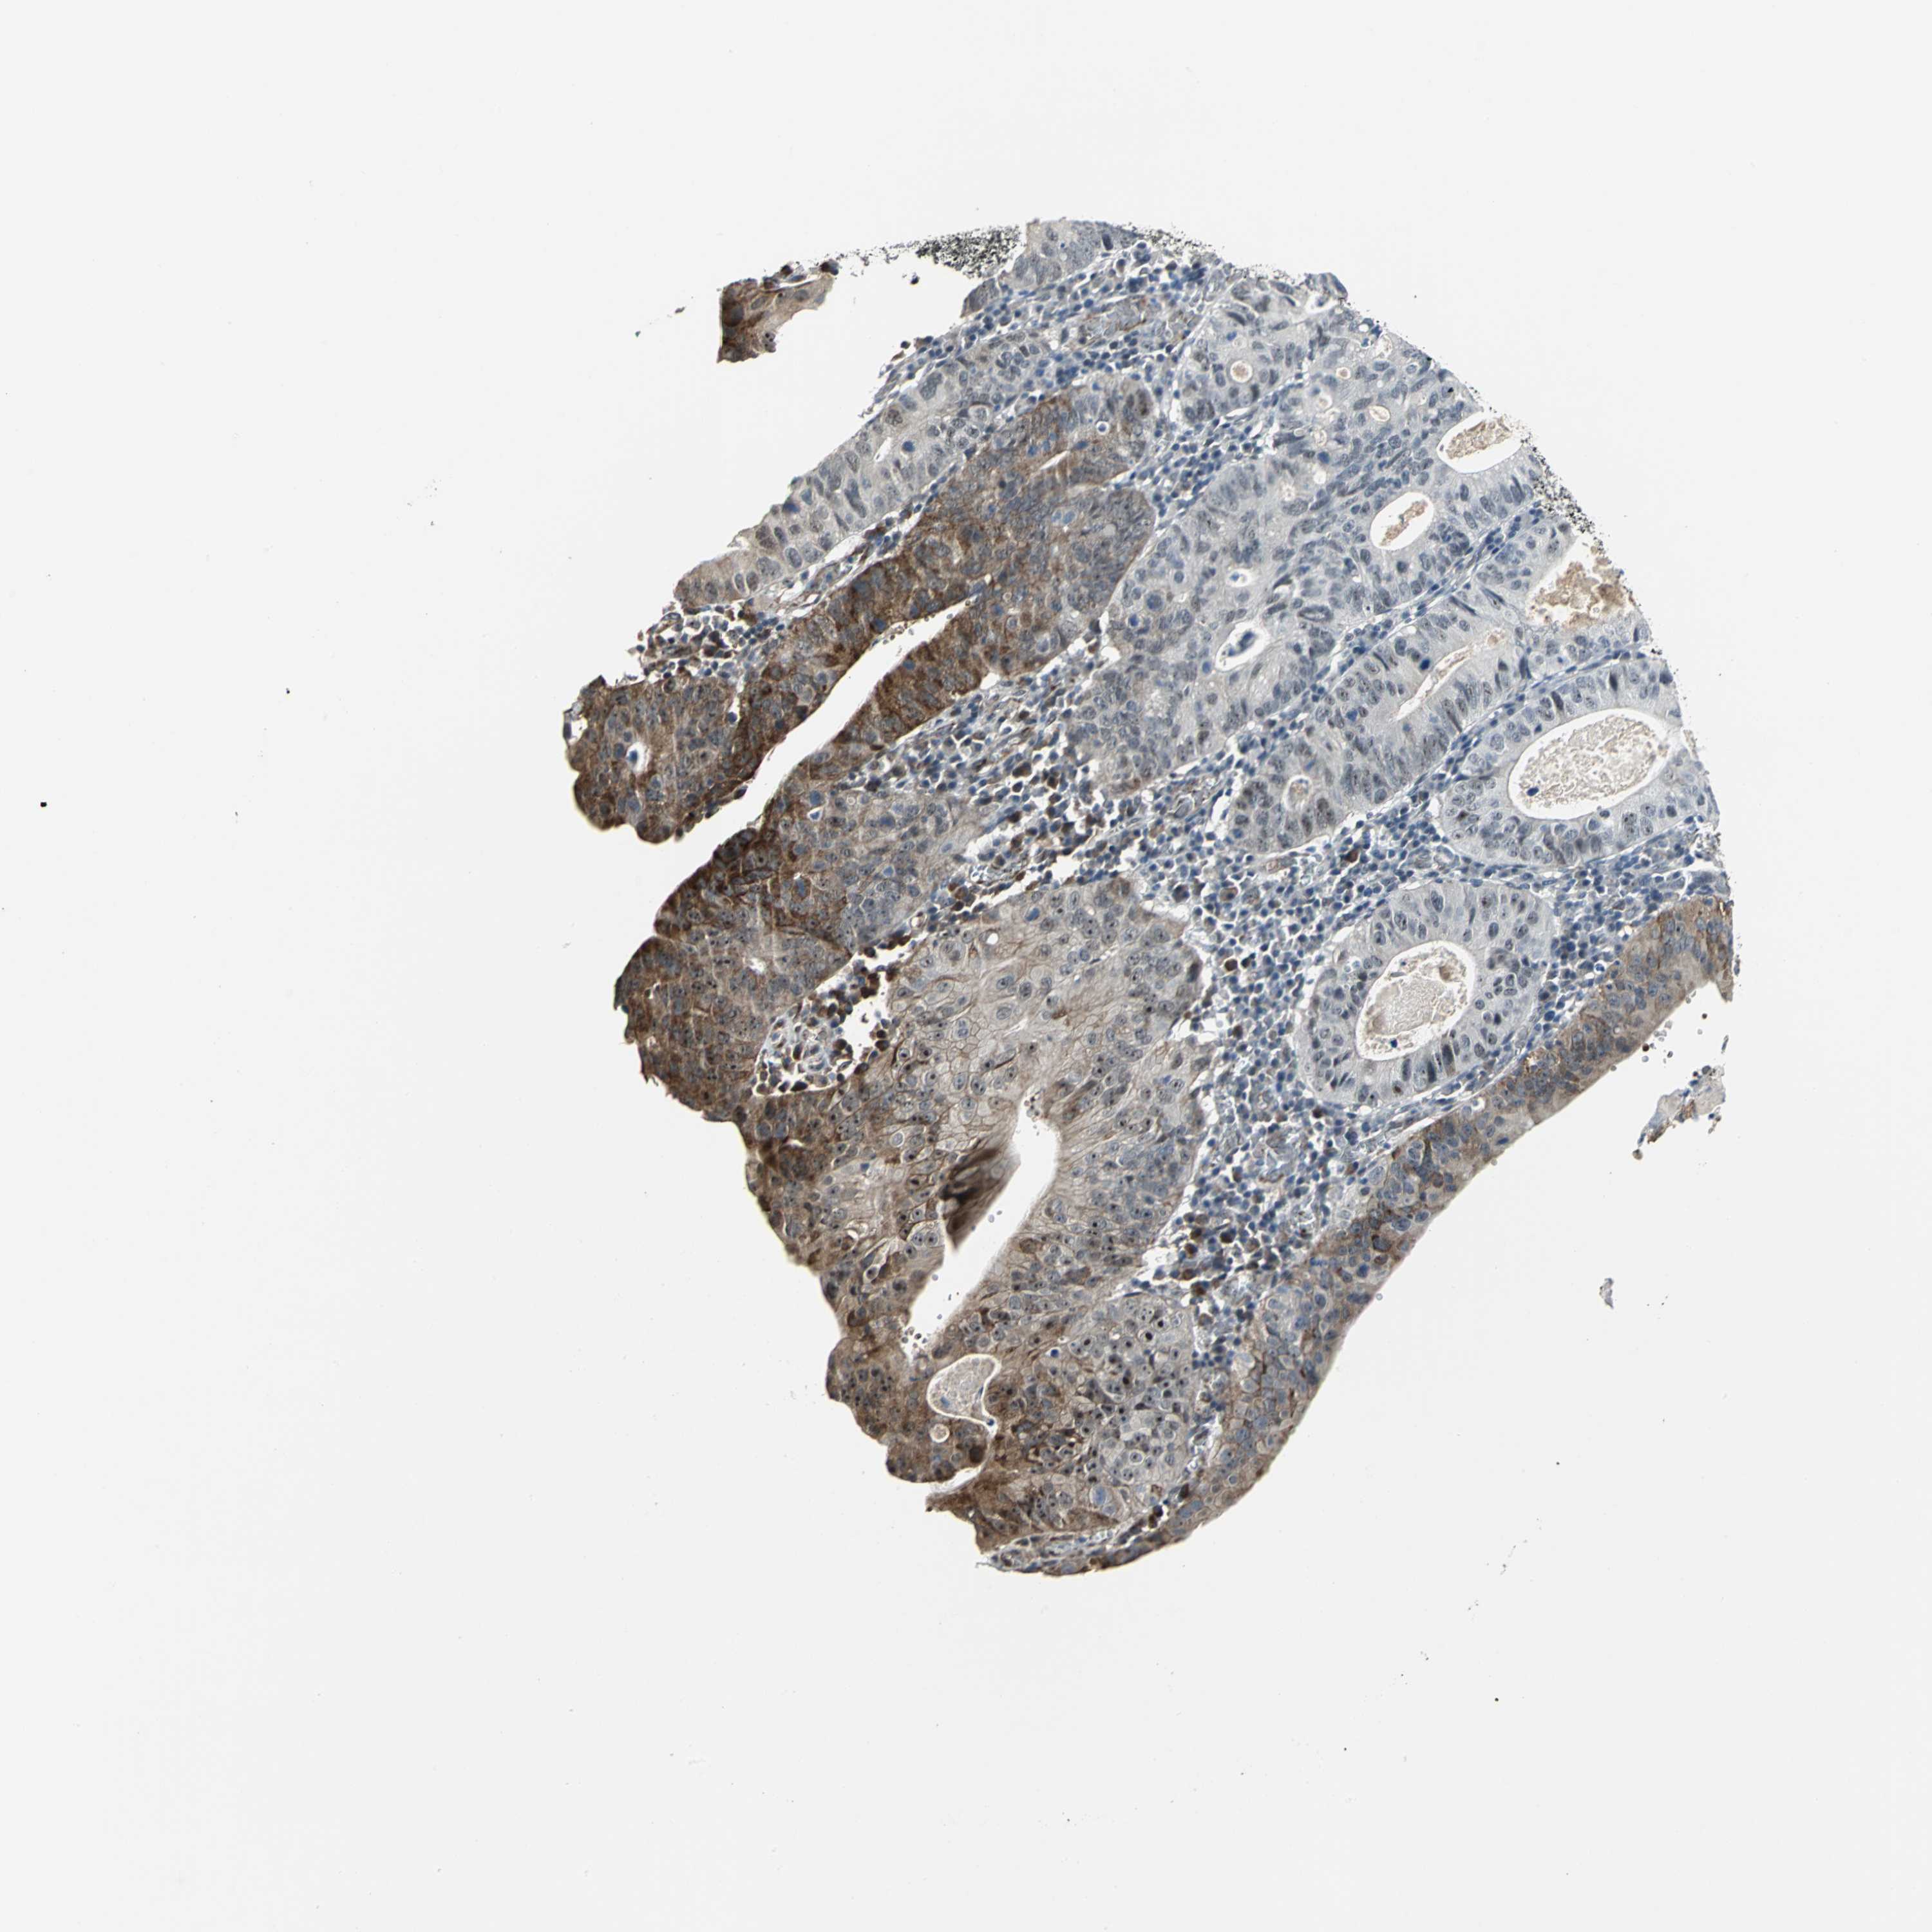

STOMACH CANCER - Protein expressioni

A mouse-over function shows sample information and annotation data. Click on an image to view it in a full screen mode. Samples can be filtered based on level of antibody staining by selecting one or several of the following categories: high, medium, low and not detected. The assay and annotation is described here.

Note that samples used for immunohistochemistry by the Human Protein Atlas do not correspond to samples in the TCGA dataset.

Antibody stainingi

Antibody staining in the annotated cell types in the current human tissue is reported as not detected, low, medium, or high, based on conventional immunohistochemistry profiling in selected tissues. This score is based on the combination of the staining intensity and fraction of stained cells.

Each image is clickable and will lead to virtual microscopy that enables deeper exploration of all samples and also displays staining intensity scores, fraction scores and subcellular localization as well as patient and tissue information for each sample.

Antibody HPA005534

Staining

High

Medium

Low

Not detected

Intensity

Strong

Moderate

Weak

Negative

Quantity

>75%

75%-25%

<25%

None

Location

Nuclear

Cytoplasmic/membranous

Cytoplasmic/membranous,nuclear

Adenocarcinoma, NOS

Adenocarcinoma, High grade